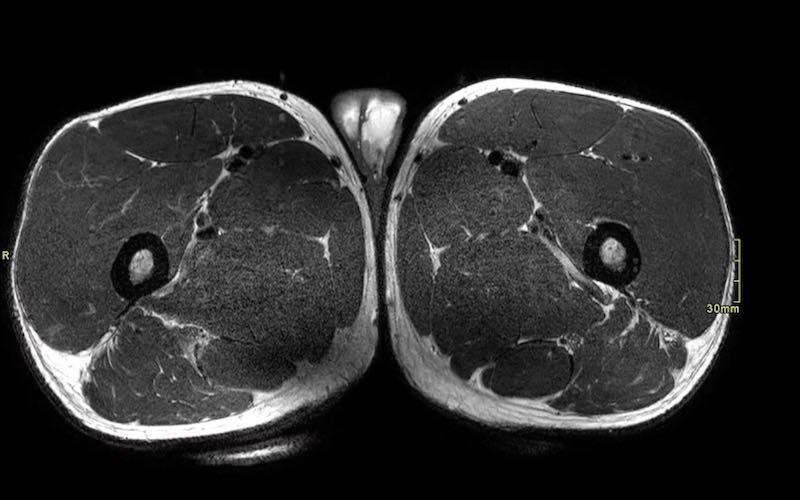

Trên các hình ảnh axial này, có thể thấy tăng tín hiệu và dày lên của gân cơ nhị đầu đùi bên trái (vòng tròn chấm vàng) khi so sánh với bên không bị tổn thương (vòng tròn chấm trắng).

Tại đây bạn có thể cuộn qua các hình ảnh axial. Có thể phóng to hình ảnh bằng cách nhấp vào chúng.

Đây là tổn thương bán phần, bắt đầu từ gân chung ở phía gần, bao gồm cả vùng MTJ và gân trong cơ ở phía xa hơn. Chiều dài vùng phù nề và mức độ biến dạng gân đều ở mức độ cao. Trường hợp này được phân loại là tổn thương BAMIC 3b/c.